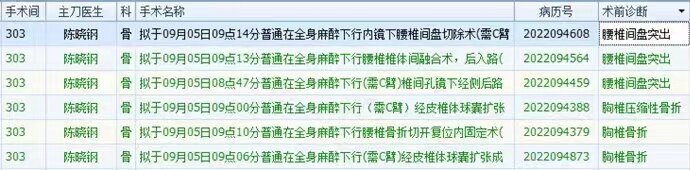

本团队率先开展腰椎微创内镜下减压融合术

在目前累计开展的130例内镜下腰椎减压融合手术中